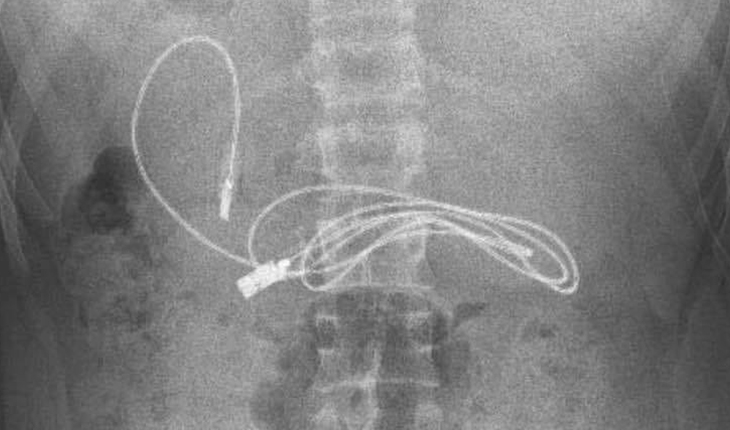

Burada da tetkik ve ön kontroller sonrası karnında yaklaşık 1 metre uzunluğunda düğümlü şarj kablosu ve lastik toka olduğu belirlenen 15 yaşındaki çocuğun tedavisine başlandı.

Gastroenteroloji Hepatoloji ve Beslenme Bilim Dalı Başkanı Prof. Dr. Yaşar Doğan ve ekibi tarafından yapılan endoskopik operasyon sonucu Y.K.'nın karnında bulunan telefon şarj kablosu ve toka çıkarıldı.

Kablonun düğümlü olduğunu ve ince bağırsağa dolandığı için zorlandıkları belirten Prof. Dr. Doğan, başarılı geçen operasyon sonrası hastayı taburcu ettiklerini ancak ilk kez böyle bir vaka ile karşılaştıklarını kaydetti.

İlk kez şarj kablosu yutan bir vaka ile karşılaştıklarını dile getiren Prof. Dr. Doğan, "Hasta bize gelmeden önce kusma ve karın ağrısı yakınmasıyla Diyarbakır’da hastaneye başvurmuş. Yapılan incelme neticesinde böyle bir durumla karşılaşınca bize gönderilmiş bir hastaydı. Kablonun siyah renk almasının nedeni, mide asidi ile uzun süre temas olmasında dolayı bir renk değişikliğine uğramış. Bu tür vakalarla çok karşılaşıyoruz fakat böyle bir kablo yutan hasta ile ilk kez karşılaşıyoruz. Dolayısıyla bize ilginç gelen hastaydı. Açıkçası biz de işlem yaparken biraz zorlandık. Çünkü kablonun bir kısmı ince bağırsağa girmişti ve kabloda düğümlenme vardı. Bu düğümlenme olduğundan dolayı bağırsakla yapışıklık meydana getirmişti. Onu çıkarırken biraz zorlandık ama çıkarma esnasından herhangi bir komplikasyon gelişmedi” diye konuştu.